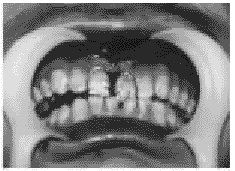

间可触及台阶样感,腭侧中线自切牙乳头至软腭处粘膜撕裂,未累及悬雍垂,左侧硬腭骨板向下移位与右侧相重叠约0.3cm。沿硬腭中线可见明显骨折线(图1、2)。初步诊断:腭中缝骨折。

图1 硬软腭粘膜撕裂,左侧硬腭骨板断端外露异向下移位